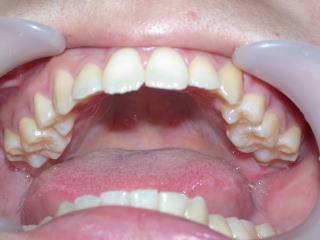

2022年7月25日初診、20代女性の叢生症例 (新潟県長岡市要町 要町歯科 歯科矯正 歯列矯正)

前歯のデコボコが気になる、とのことです。

2024年5月15日装置除去

術前術後

2022年7月→2024年5月(2年弱でした。これから保定期間に入ります。)